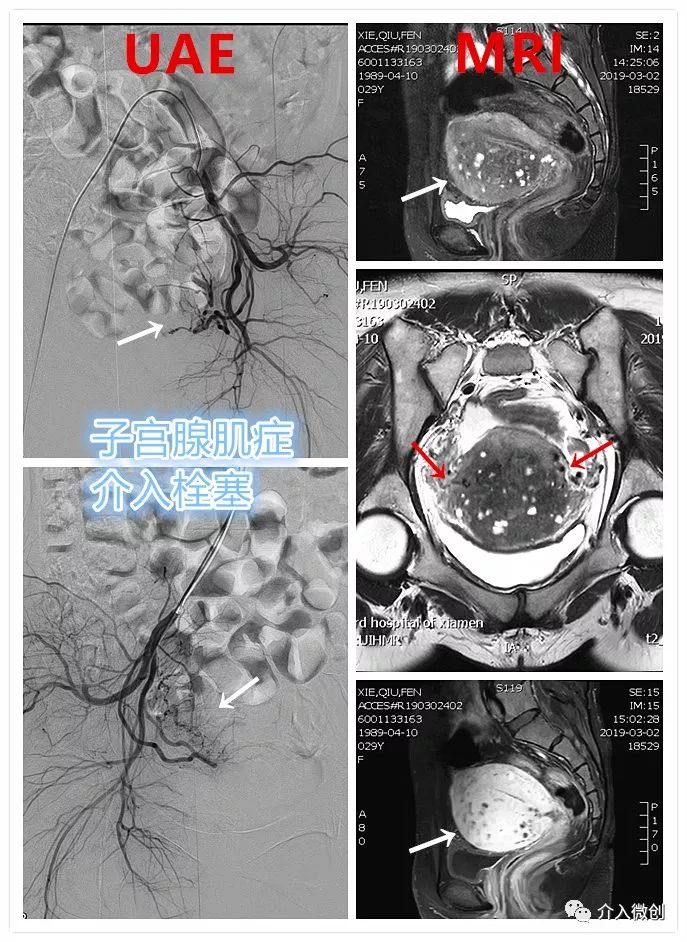

子宫动脉栓塞术(UAE)

子宫腺肌病的介入治疗(UAE)与治疗机制

一般以右侧大腿根部的股动脉作为穿刺点,穿刺进入人体动脉血管系统,因为人体动脉血管是相通的,所以可以通过这个穿刺点,将细小的导管分别送达两侧子宫动脉(子宫腺肌症病灶的供血动脉),经导管注射非常微小的PVA颗粒或微球(300-500um),造成病变组织营养和养分供应中断,进而异位子宫内膜坏死脱落,分泌前列腺素减少,缓解痛经,减少月经量,从而达到治疗目的。

年轻患者,患有“子宫腺肌症”8年余,长期受痛经困扰,严重影响生活及工作。经历药物调理及多种药物止痛、“曼月乐”宫腔植入等多种治疗,痛经症状日益严重。经介入微创治疗后,术后痛经症状即得到明显缓解。

- 术前子宫MRI提示子宫明显增大,诊断为“子宫腺肌症”。UAE术后1月,痛经症状得到明显缓解。